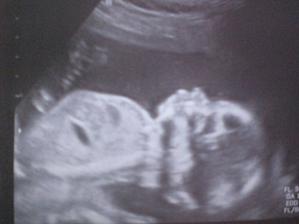

Náš drobeček...

focení v 33t.tt :-